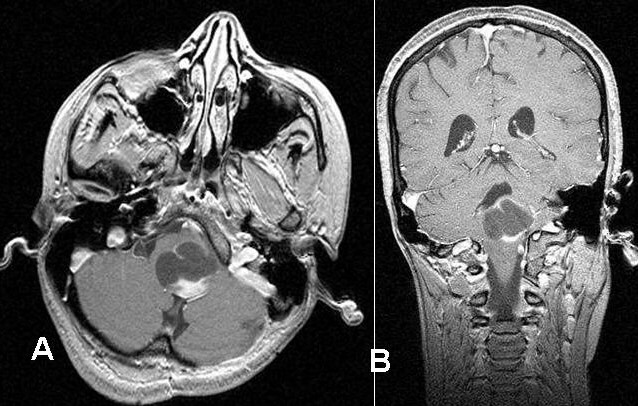

Radiology of meningiomas typically show a spherical mass linked to the dura is seen through imaging.

In the head, the vestibular cochlear (VIII) nerve at the cerebellopontine angle is most usually involved by schwannomas.

Bilateral schwannomas are often seen in patients with neurofibromatosis type II (NF2).